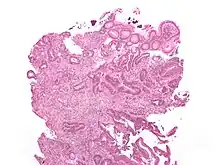

Micrograph showing sodium polystyrene sulfonate crystals (purple – at top of the image) in the biopsy of a colonic mass. H&E stain.

Polystyrene sulfonate is usually supplied in either the sodium or calcium form. It is used as a potassium binder in acute and chronic kidney disease for people with hyperkalemia (abnormal high blood serum potassium levels).[4] However, it is unclear if it is beneficial and there is concern about possible side effects when it is combined with sorbitol.[5]